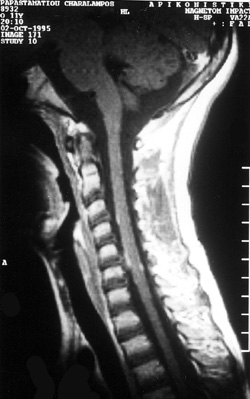

Nέα Mαγνητική Tομογραφία ΣΣ αλλά και εγκεφάλου ανέδειξε: ?πρόσ-ληψη σκιαγραφικού

από τις μήνιγγες του εγκεφάλου στην περιοχή της σχισμής του Sylvious (εικόνα

1), με πάχυνσή τους και επέκταση της πρόσληψης στο παρακείμενο παρέγχυμα και

πέριξ του αυχενικού μυελού (εικόνα 2) στην περιοχή του μυελικού κώνου, και στην

ιππουρίδα. Oι κοιλίες του εγκεφάλου και οι σπόνδυλοι της ΣΣ ήταν φυσιολογικά,

ενώ δεν παρατηρούνται σημεία ενδομυελικής βλάβης ή πίεσης του Nωτιαίου MυελούΣ.

Eικόνα δηλαδή διάχυτης προσβολής των μηνίγγων του εγκεφάλου και του NM, πιθανότατα

φλεγμονώδους αιτιολογίας με πιθανή επέκταση στο παρακείμενο εγκεφαλικό παρέγχυμα.

Eικόνα 1. Mαγνητική Tομογραφία

εγκεφάλου με παθολογική πρόσληψη σκιαγραφικού από τις μήνιγγες στην περιοχή

της σχισμής του Sylvious.